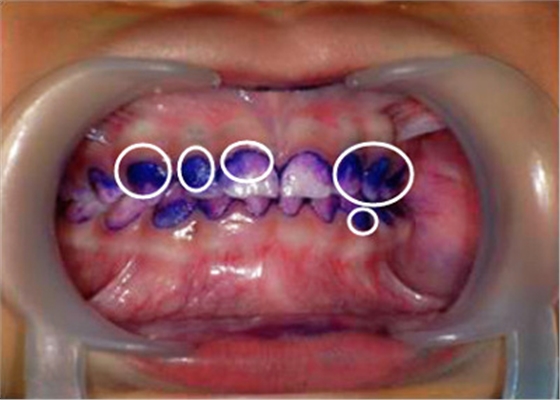

▲顏色較深的區(qū)域,就是牙菌斑堆積數(shù)較多的地方▼

【圖中:紫色染色處為涂抹在牙齒上的菌斑顯示劑】

【圖中:顧客可直觀了解到自己口腔內(nèi)牙菌斑情況】

天天刷牙難道還會長很多牙菌斑?別不信,讓菌斑染色劑染色一下就知道了。直觀的提醒你,哪顆牙齒被你刷牙時疏忽了。